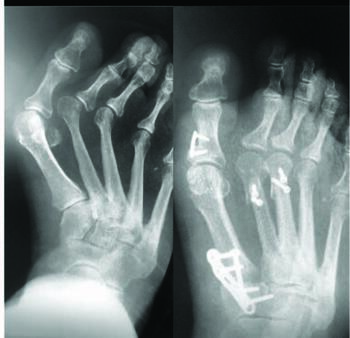

Osseously mature patients with symptomatic metatarsal parabola pressure imbalances, midfoot deformity, and hallux valgus may benefit from a multilevel surgical reduction. In my experience, there is a high prevalence of, and clinical correlation between, metatarsus adductus and hallux valgus in adults. Accordingly, I find that complete correction of this pathology and its associated symptoms can prove elusive as we have not had a reproducible approach to lesser TMT midfoot deformities. Descriptions of various soft tissue and osseous procedures to correct these compound foot deformities exist, and have mixed results. There are also descriptions of techniques utilizing free-handed proximal and distal osteotomies of the lesser metatarsals to address severe metatarsus adductus with hallux valgus. Still, the radiographic results are inconsistent and often result in residual deformity (see left set of photos above).20 Rotational and translational osteotomies through the metatarsals can disrupt the weight-bearing parabola.21 Combined medial column lengthening and lateral column shortening procedures also reveal varying degrees of success.22 These procedures can produce overtightening of the plantar soft tissues with overactivation of the windlass mechanism and in contrast, instability of the TMTs through an oblique axis shift in ligamentous alignment.22,23